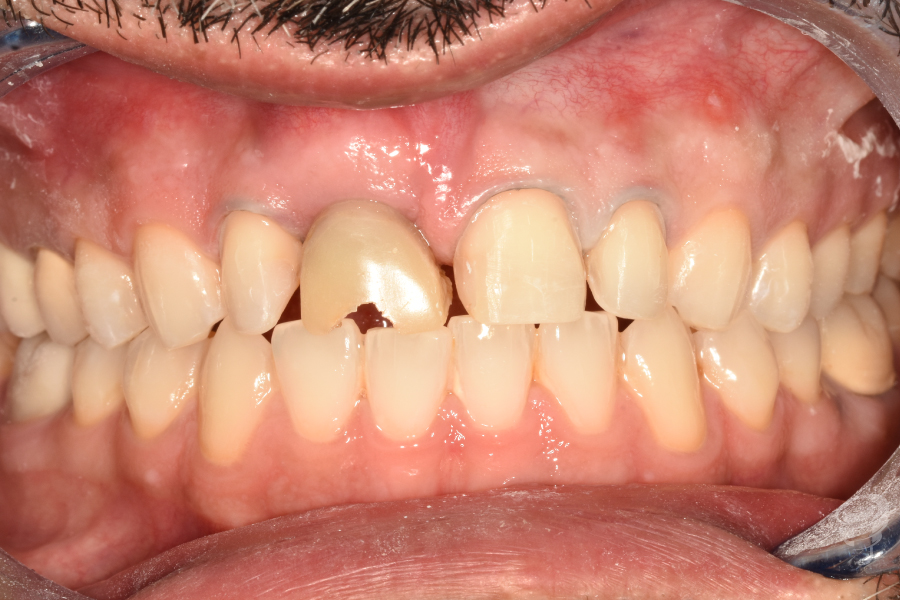

Figura 2